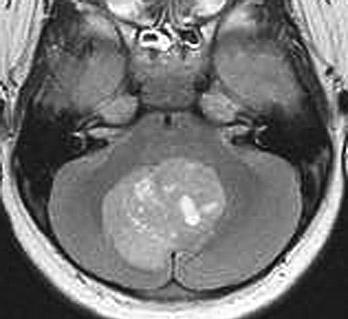

The axial MRI scan above and the enhanced MR scan below demonstrate a medulloblastoma in a child. These tumors tend to occur in the cerebellar vermis, with a peak incidence in the first two decades of life.